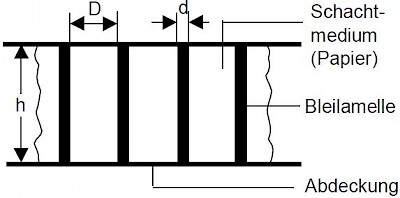

Raster bestehen aus Absorber-Lamellen der Dicke d und der Höhe h, die in regelmäßigen Abständen D nebeneinander angeordnet sind. (Siehe Abb. re)

Raster bestehen aus Absorber-Lamellen der Dicke d und der Höhe h, die in regelmäßigen Abständen D nebeneinander angeordnet sind. (Siehe Abb. re)

Zwischen den Absorber-Lamellen befindet sich ein schwach absorbierender Stoff, das Schachtmedium, das kann Papier, Kunststoff oder Aluminium sein.

Das Lamellen Material ist meist Blei kann aber auch Wolfram sein. Die Abdeckung besteht aus Aluminium oder Kohlefaser mit Kunststoff.

Anzahl der Lamellen: Je cm N werden auch Linienzahl (Liniendichte) genannt: N = 1 / ( d + D) pro cm

Schachtverhältnis: r ist das Verhältnis von Lamellenhöhe zu Lamellenabstand: r = h / D - gängige Schachverhältnisse sind 6, 8, 10, 12.